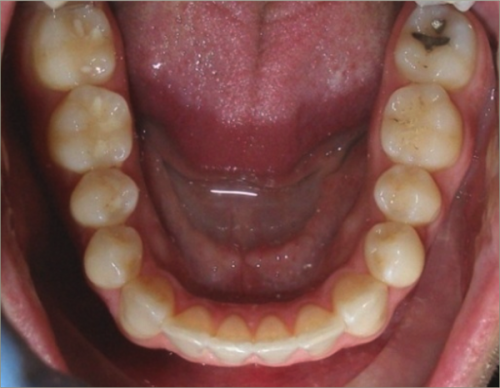

30 year old male:

Diagnosis:

- Upper and lower crowding

- Narrow upper & lowerarch forms

- Open bite

Treatment:

- Invisalign

- Non-Extraction

- 27 months